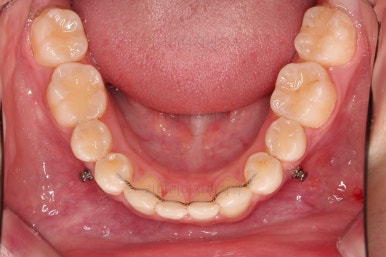

치아 갯수를 맞추고 튀어나온 앞니를 넣기 위해서 윗니 중간의 작은 어금니를 발치를 했고요.

아래는 통째로 앞으로 끌고 나오기로 했습니다.

아래턱은 아쉽게도 성장 시킬 수 있는 나이는 지났고, 대신 가능한 선에서 아랫니를 앞으로 빼보기로 했습니다.

아랫니는 이후에 어금니를 앞으로 당겨오면서 빈공간을 줄여 나갑니다.

교합이 잘 맞아졌고요.

위아래 앞니도 서로 가까워졌어요.

치열도 가지런해졌고, 과개교합도 잘 개선이 되었습니다.